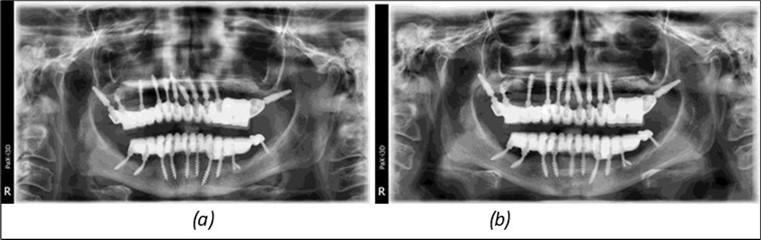

A total of 11 implants is placed in the maxilla, including compressive TPG implants with a polished surface in the maxillary-sphenoid fusion area (Figure 3, Figure 9). Similarly, in the anterior region, final fixation is achieved in the nasal cortex, and BCS corticobasal implants are added in areas with massive bone loss in the frontal region (Figure 3, Figure 8, Figure 11). Additionally, in the palatal sinus cortical area, with the aim of avoiding the addition and sinus lift zone where the second cortical bone no longer exists, 3 implants are placed, 2 in quadrant 1 and 1 in quadrant 2 (Figure 3, Figure 8). Through the Caldwell-Luc sinus lift procedure, the sinus cortical bone is displaced to allow the placement of the graft material and elevation of the sinus membrane. This sinus cortical is no longer recreated at the junction of the graft material and mucosa-sinus membrane, making it impossible to place a corticobasal implant, which relies on the second cortical bone. In the distal mandibular area, after the removal of two stage implants due to massive destruction in quadrant 3, implant placement distal to the mylohyoid line is not possible, as in quadrant 4 (Figure 10). A re-intervention occurs after 5 months to stabilize the area (Figure 12, Figure 14). Also, at the moment of fixation, the tip of one implant fractures, and the decision is made to leave it in place due to regional bone destruction, in order to avoid enlarging the bone defect.

Figure 14.Rx panoramic final situation control: (a) Panoramic X-ray with the addition of a distal BCS implant in quadrant 3 at 11.2022; (b) Control X-ray, 10.2023.

The results of rehabilitation treatment with corticobasal and compressive implants with a polished surface after the failure of two stage implants were highlighted over a period of 3 years and 3 months as being very good (Figure 14, Figure 15), with the patient completing a satisfaction survey in this regard. Certainly, it is necessary to continuemonitoring these results in the long term.